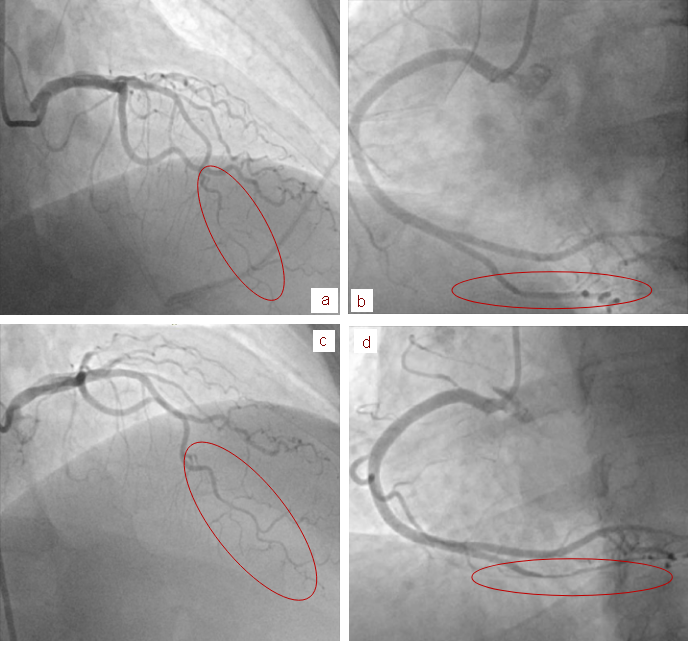

患者被诊断为ACS,接受了急诊冠脉造影,造影结果显示左前降支(LAD)影像模糊,血管直径突然变细,延伸至LAD远端和对角支(图2a)。虽然没有清晰地看到冠脉内的内膜瓣,但在LAD的中段至远段可见弥漫性血管狭窄,高度怀疑冠状动脉夹层。造影剂在冠状动脉远端能够迅速充盈和清除(TIMI 3),并且在冠状动脉内应用硝酸甘油

后,管腔直径无变化。所有冠状动脉都没有血管粥样硬化的证据,也没有LAD以外冠状动脉狭窄的证据。在冠脉造影操作过程中,患者胸痛缓解,心电图显示ST段升高正常。考虑到患者血流动力学稳定,LAD远端的血流正常、胸痛缓解,并且怀疑为冠脉夹层,医生选择给予患者保守治疗。

图2 患者冠脉造影影像(a和b:初始造影影像;c和d住院第6天复查造影影像)

在住院期间,患者未再发作胸痛。由于诊断仍不明确,医生在入院第6天再次进行冠脉造影以评估疾病的进展。血管造影

结果显示, LAD病变完全消失(图2c),与解剖一致。与最初的血管造影影像相比,雾度不再存在,并且血管朝着顶端LAD逐渐变细。然而,与最初的冠脉造影影像相比,右冠后降支(PDA)出现了新的狭窄,血管直径突然变细(图2d),但血流正常。医生考虑再次新发冠脉夹层,患者在整个住院期间未再出现症状,患者被安排出院,门诊随诊。